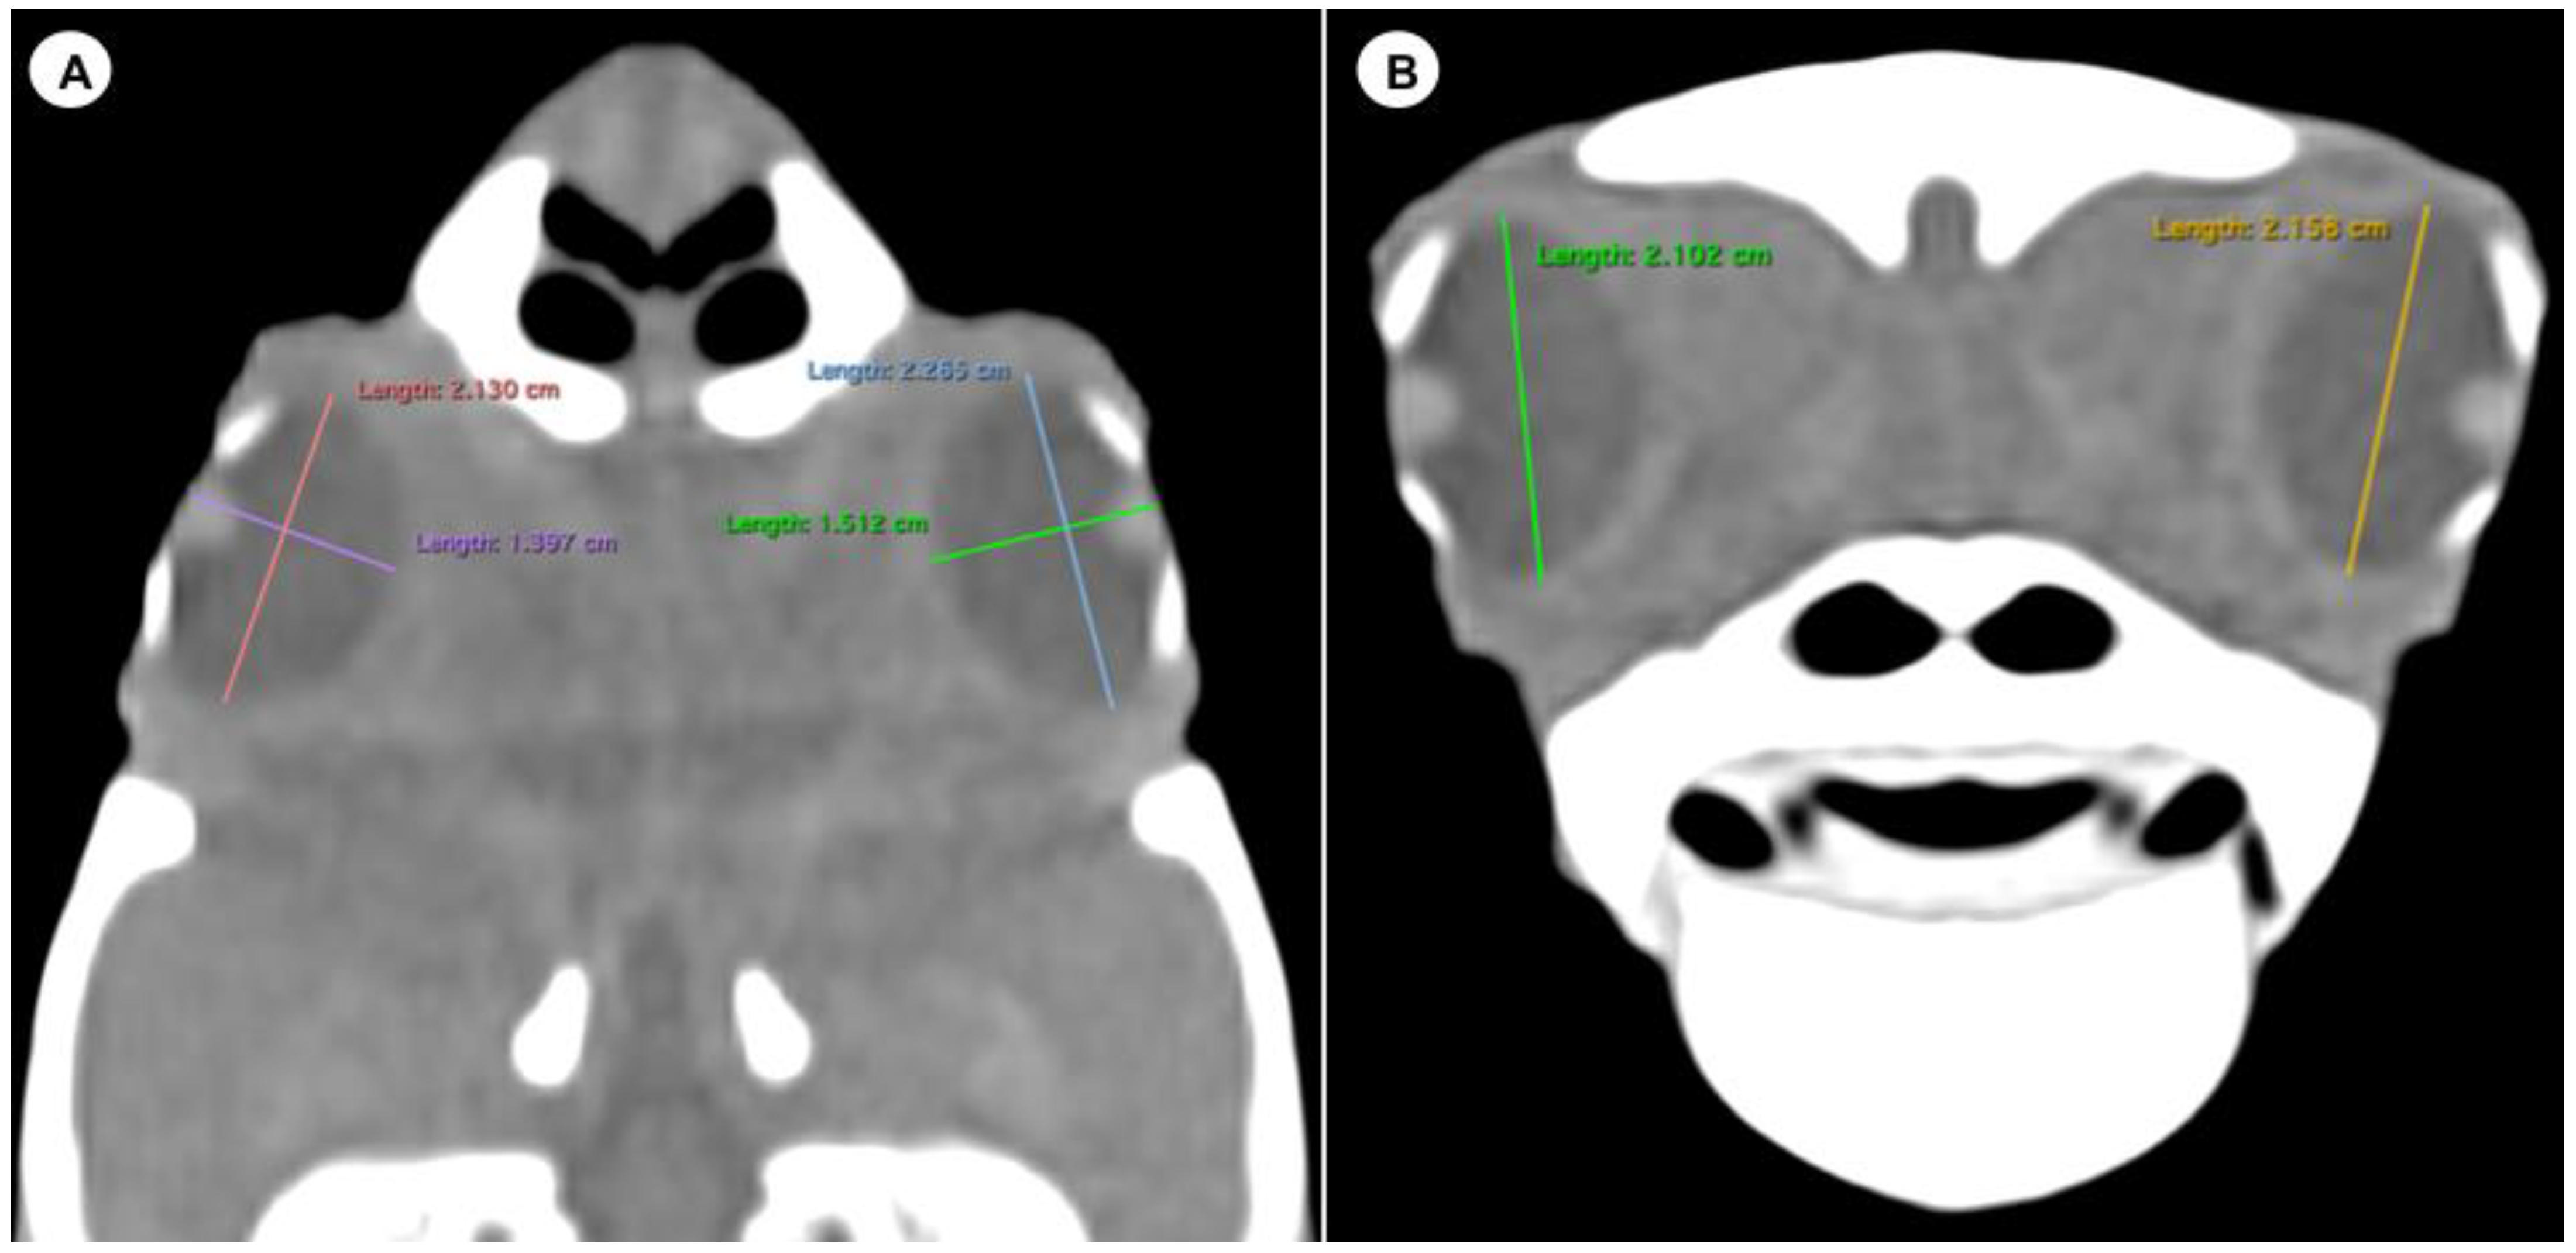

- Height of the eyeball or distance between the most dorsal and the most ventral portion of the eye (Figure 3B).

Figure 3. Dorsal multiplanar reconstruction (MPR) and transverse CT images in soft tissue windows of the head with measurements of the length, width (A), and height (B) of the eyeball of the C. caretta head. - -

Last, the eyeball presented a mean height of 22.23 mm (range = 15.9–27), a mean width of 15.77 mm (range = 12–19.2), and a mean length of 22.83 mm (range = 16–27.9).